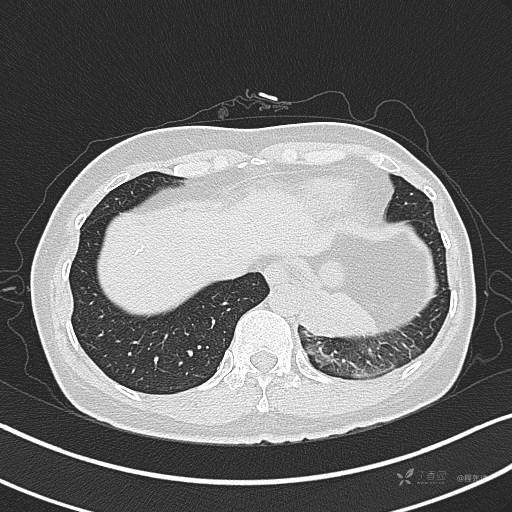

纵隔窗

病灶平扫CT值约31HU